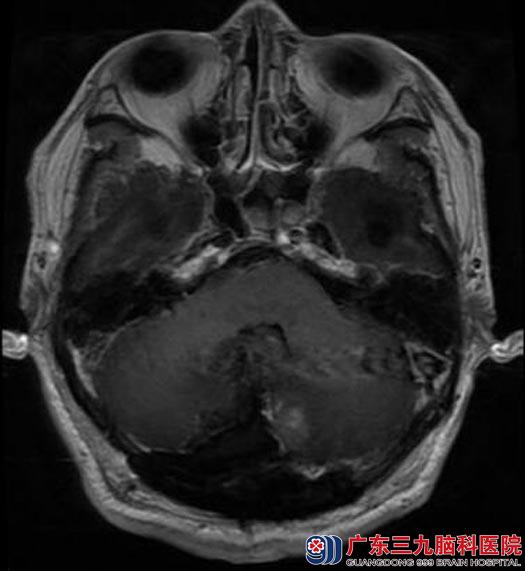

广东三九脑科医院进一步头颅MR检查提示:后颅窝小脑幕右侧幕下脑外占位性病变,大小约为4.1cm×4.7cm×4.2cm,考虑为脑膜瘤;并幕上梗阻性脑积水及小脑扁桃体下疝形成;头颅CTA提示:后颅窝右侧幕下占位性病变血管丰富。